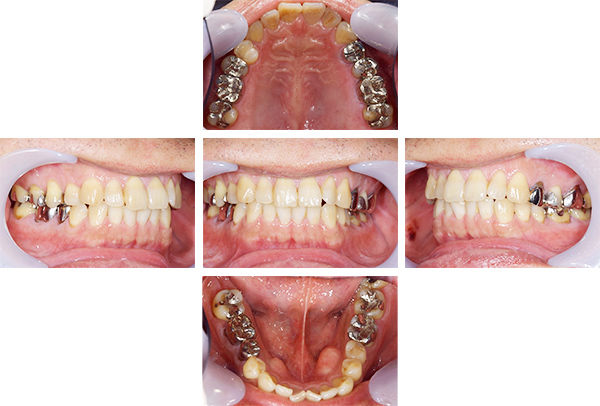

歯列矯正・インレー・クラウン症例

前歯が黒っぽいのが気になる、

悪いところは全部治したい

年齢 54代女性

主訴 歯をきれいにしたい

治療

期間

4年

費用 セラミックインレー 12本

660,000円

オールセラミックプレミアムクラウン 3本

495,000円

矯正 874,900円

計 2,029,900円(税込)

※全て税込となります。

症例写真(治療前)

担当医師所見

治療前:

八重歯が目立ちます。また銀歯もおおく、見た目が気になります。虫歯も散見できます。

レントゲン写真(治療前)

根の治療を3本すでに治療されています。1本根の奥の詰め物が疎になっていますので、根の部分の再治療も行う必要がありそうです。銀歯の中で虫歯になっているものもあります。

治療中

矯正装置をつけています。だんだん八重歯が動いてきているのがわかります。今回のケースでは、抜歯を行わずに矯正ができました。

症例写真(治療後)

治療後:

矯正治療と虫歯の治療すべて終わったときの写真になります。見た目も最初の頃とは全く違いますし、お口の中もすごく綺麗です。

方針

まずは虫歯の治療を行い、被せ物をする部分は仮歯をいれて矯正を行う。矯正終了後、仮歯の部分を最終的な被せ物に変えていく。また気になっていた銀歯もセラミックに変えて終了となった。

内容

セラミックインレー、オールセラミックプレミアム、矯正

特記

事項

虫歯の治療によって歯が一時的に染みるようになる可能性があります。また、歯を抜かずに矯正を行っていますが、全ての方で歯を抜かずに矯正ができるわけではありません。

治療リスク・副作用

・詰め物を銀歯からセラミック等のインレーに変えると、歯がしみることがある

・被せ物をやりかえる時は中で大きく虫歯になっていたり、歯が割れている場合は抜歯になることもある

・インプラント治療は骨と結合するのに期間がかかるが、個人差がある

・ホワイトニング後は歯がしみることがある

・詰め物、被せ物をする時は自分の歯を削ることになります